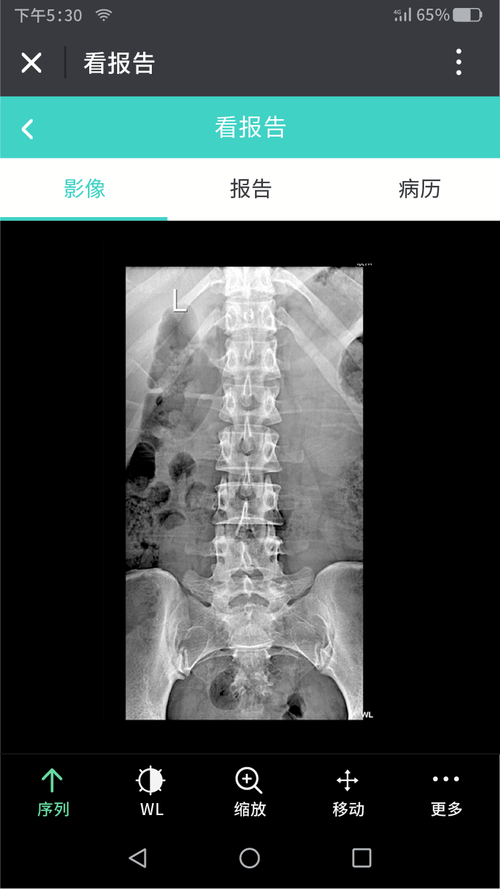

如果你使用过网盘,享受过云存储的服务,相信你一定知道“云胶片”的便捷之处,云胶片就是存储在云空间的胶片,医生或者患者在不打印胶片的情况下,就可以通过手机、电脑云端进行查看。

而OKI所有的医疗行业打印机,都可以实现云胶片打印的无缝连接。这样,患者不但可以拿到握在手里才踏实的传统胶片,还可以在方便地在云端随时查看自己的片子,两全其美。